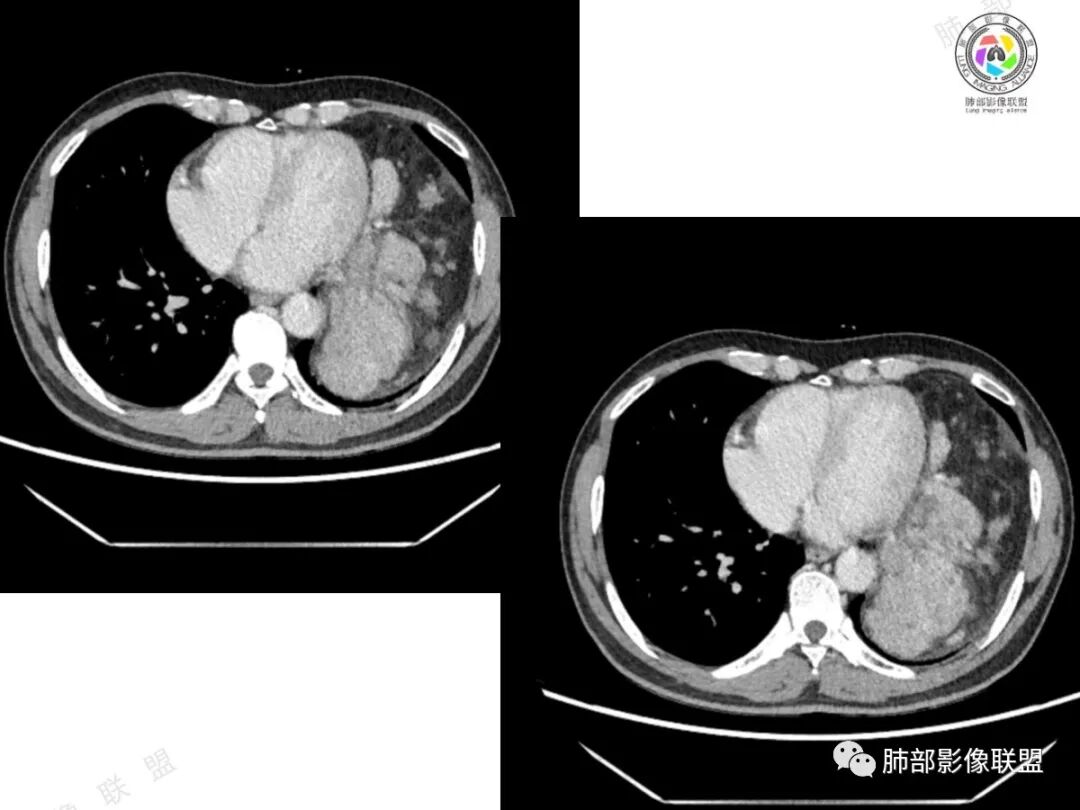

2、影像所见:左侧纵隔紧贴心包铸型生长巨大混杂密度肿块,边界清楚,临近结构受推挤移位,无明显外侵征象。肿块自主动脉弓旁一直顺延到至膈顶,呈“垂乳征”。病灶脂肪成分居多,斑片状、结节状及团块状实性密度成分散落其中,呈地图样分布,实性成分偶见低密度线样分隔,未见明确钙化影。增强扫描实性成分呈延迟明显强化,并见强化血管影。纵隔内有肿大淋巴结,未见胸腔积液,肺内及胸膜未见转移性病灶。

右侧中后纵隔肿块,病变形态不规则,似多结节堆积,周围伴有环形脂肪密度,平扫密度尚均匀,增强后不均匀强化,部分强化明显,坏死不明显,周围淋巴结肿大,病变向左肺压迫,左肺体积缩小,左心室壁增厚,综合考虑:低度恶性,脂肪肉瘤,脂肪母细胞瘤,畸胎瘤(钙化没有),鉴别脂肪沉积。

这个肿瘤生长跨度有点奇特,成分很混杂有强化,但侵袭性不强,似有包膜包裹,含脂,巨大,跨度非常大,有点跨胸腹腔的感觉,成分非常混杂,强化也很杂乱,但外有包膜边缘光滑清晰无侵犯,而且无症状,年纪又是中老年,肿块有种征象内外矛盾,与症状矛盾,呈现我很‘’丑‘’但很‘’温柔‘’的感觉,故考虑继发的,偏良性的病变,首选冬眠瘤;其次畸胎瘤。

临床无特异性。定位:左侧纵膈没问题,实性部分紧贴心缘,行走的血管看不出起源,左侧锁骨下动脉?影像特点:1 脂肪成分肯定增多,以成熟脂肪为主,部分脂肪浑浊,这点排除胸腺瘤?也排除无脂肪变化的淋巴瘤?2 实性部分分布于心缘侧,部分被心缘塑形,病灶较软?良性的证据?3 实性部分呈结节状,有纤维分割?病灶内行走的血管,无明显受侵表现,排除淋巴瘤后,说明病灶是良性病变?4 病灶巨大,而临床逍遥,周边也明确的 转移侵犯表现,提示良性可能大?5 无骨化或钙化。综合良性病灶可能大,血管平滑肌脂肪瘤可能大,不完全排除脂肪肉瘤。病灶底部有渗出?出血?感染?良性恶变?。

中老年男性,偶尔胸痛,症状相对轻。左侧胸腔巨大混杂密度肿块,与纵隔相连,呈悬乳征,内见脂肪密度及多发散在结节状及团块状软组织密度影,增强扫描有强化,并见强化血管影。病变边界清楚,周围侵犯不明显。常规考虑胸腺脂肪瘤。但是病灶内软组织成分强化明显,右肺门和隆突下似乎有肿大淋巴结,患者又有胸痛的症状,且年龄偏大,脂肪肉瘤要鉴别一下,因为胸腺脂肪瘤绝大多数发生于40岁以下,残留胸腺的软组织影一般较少,呈条状或者片絮状,本例软组织成分太多了,加上有强化血管影,所以需要脂肪瘤和脂肪肉瘤鉴别。再离谱点儿就是有没有可能同时合并胸腺瘤,因为软组织部分分隔明显。

中老年男性,左侧纵隔巨大混杂密度肿块,与心包分界欠清,其内多发大小不等实性成分及脂肪密度影,增强实性成分不均匀强化,病灶内可见血管,考虑胸腺脂肪肉瘤可能。